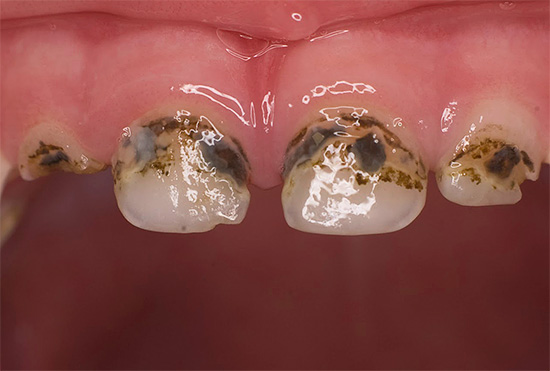

La seguente foto mostra un tipico esempio di carie di bottiglie:

Nella foto sotto - tipica carie di bottiglie in una fase avanzata di sviluppo. In alcuni punti, lo smalto dei denti è completamente collassato e sono visibili lesioni profonde della dentina, che si scuriscono rapidamente a causa della pigmentazione di vari coloranti alimentari e prodotti di scarto di batteri:

Nelle prime fasi, la carie di bottiglia può manifestarsi sotto forma di punti chiari opachi (stadio di una macchia bianca o di gesso), che nel tempo assumono la forma di rugosità sullo smalto, gradualmente si approfondiscono e si scuriscono.

Di norma, la carie di bottiglia colpisce prima i quattro denti superiori anteriori del bambino. Il processo cariato spesso inizia nella zona gengivale, copre rapidamente l'intero dente attorno alla gengiva lungo il perimetro e penetra negli strati profondi di smalto. Il danno alla zona gengivale del dente è una caratteristica della carie in bottiglia.